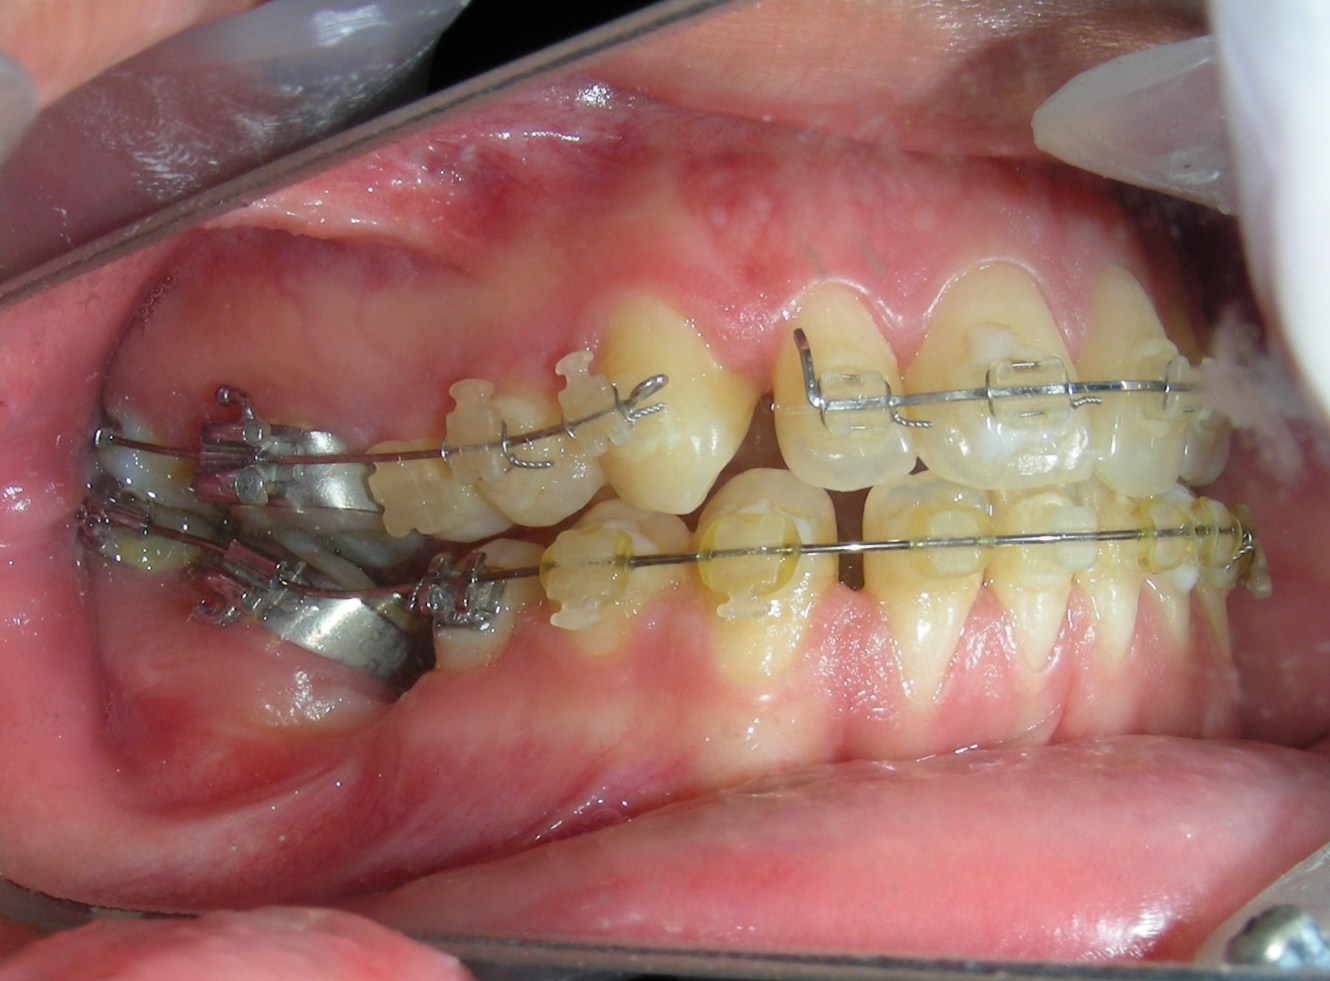

Was installed a Hyrax-type 10mm palatal expander of the Brazilian trademark Morelli® , modified by the author to be adapted to receive TADs microscrews, in order to initiate maxillary disjunction with MARPE (Mini-implant Assisted Rapid Palatal Expansion), TADS was installed with skeletal anchorage placed bilaterally having as references the roots of the maxillary canines and first premolars. Prior to insertion, local infiltrative anesthesia was administered using 2% lidocaine hydrochloride with 1:100,000 epinephrine. A total dose of approximately 0,8 mL per side (cortical infiltration technique). The TADs were inserted under aseptic conditions using a manual driver. Microscrew Evolution 1,6 Ø x 10 mm from the Argentine brand Odontit® . The Hyrax expander was then fitted and activated after 48 hrs .

Protocol of one activation per day was followed for a period of three weeks where the first clinical and radiographic evaluation was performed, showing clear signs of skeletal expansion, including the presence of a midline diastema. One more week of activations was added with a total of 28. The patient reported moderate headache during the first week of activation.

Having successfully achieved the expansion, we proceed to the intrusion of the posterior superior sectors, modifying the Hyrax by adding anchoring hooks at the buccal level of the first premolars. Using the Hyrax as anchorage, we sought a parallel intrusion. This could be replaced by a palatal bar. TADs were installed bilaterally at the mesial level of the first molars, inserting them as parallel as possible to the roots.

Simultaneously we begin with the alignment of the lower arch ,Simultaneously we began with the alignment of the lower arch with Roth prescription ceramic braces .022 . Henry Schein®

As the reader may infer, alignment and leveling of the upper anterior segment are being intentionally deferred at this stage of treatment. This strategic decision is based on the primary objective of closing the anterior open bite not through anterior extrusion, but by means of controlled posterior intrusion. This biomechanical approach promotes a counterclockwise rotation of the mandible, which leads to a increase in the facial axis angle and improvement in vertical facial proportions. By avoiding early anterior alignment, we prevent any premature vertical displacement of the upper incisors.